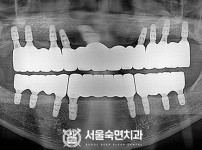

임플란트-전후사진2

치과를-선택할-때-꼭-확인하세요-서울숙면치과-임플란트-전후사진